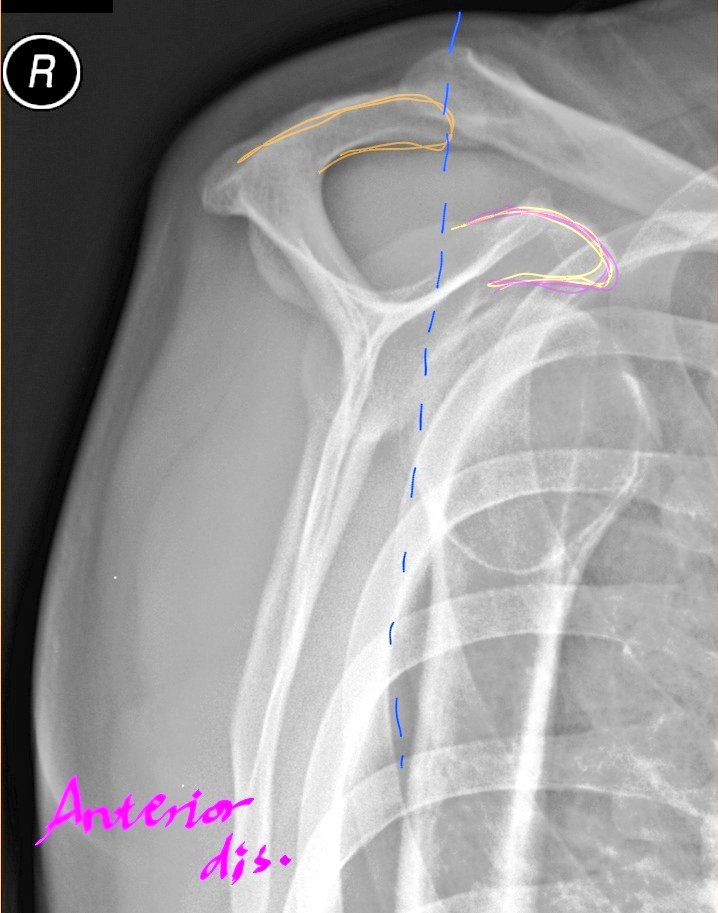

Scapular Y view lateral (Anterior Oblique position of shoulder)

•الخلع:هو خروج عظمة الذراع من مكانها الطبيعي لتتحرك نحو الأمام(وهو الأكثر حدوثاً)أو الخلف(أقل حدوثاً).

ويتم تقييم النوع من خلال موقع

Head of humerus

في حالات الخلع(الأمامي):

(Anterior dislocation)

Humeral head will be inferior to coracoid process.

الخلع الخلفي:

(Posterior dislocation)

Humeral head will be inferior to acromion process.

لاحظ موقع humeral head

بالنسبة لل

Acromion(orange) and Coracoid(violet)

●الوضع:

يكون المريض في وضع

Anterior Oblique

بحيث يكون وجهه ناحية الكاسيت.

•يشكل المريض زاوية بكتفه المصاب مع الكاسيت حوالي ٤٥°إلى٦٠° بحسب حجم جسمه والهدف جعل scapula

بشكل true lateral.

•إذا أمكن إبعاد الذراع للخارج قليلاً وليس لفها بهدف إبعادhumeral head عن الأضلاع.

CR:منتصف